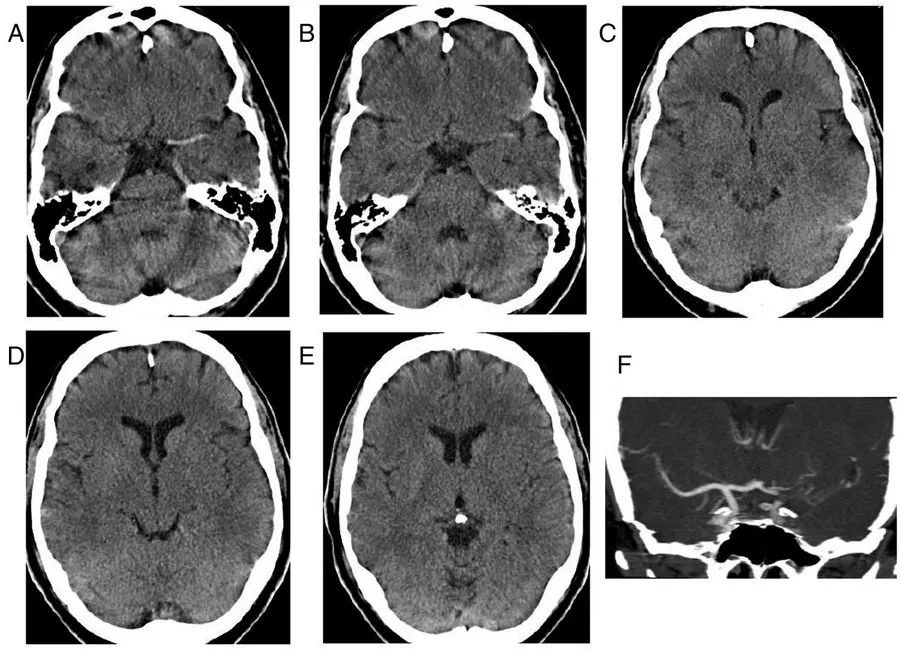

图1  60岁男性,急性缺血性脑卒中,A~E:CT平扫;F:血管造影冠状位重建

左侧颈内动脉末端、大脑中动脉及其大脑外侧裂的分支可见高密度血栓影。大脑中动脉高密度征的特异性几乎为100%,但敏感性只有5%~50%。

此外,左侧大脑外侧裂周围皮质可见界限不明确的稍低密度影,豆状核模糊,反映了早期缺血性改变。CT血管造影证实左侧颈内动脉末端、大脑中动脉的M1段和M2段闭塞,远端可见少量侧支循环血流。